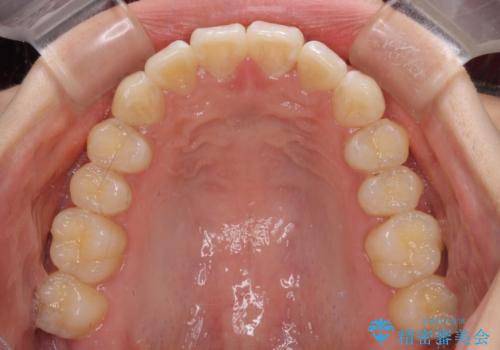

上下前歯の叢生をインビザラインできれいに

- 前歯のデコボコを気にして来院された患者様です。

前歯が重なっていることで口元が閉じにくくなっていたため、歯列全体の側方への拡大と、歯と歯の間を少し削ってスペースを獲得することとしました。

下顎前歯は後戻りを起こしやすいため、舌側を細いワイヤーで固定し、マウスピース型リテーナーで保定を行うこととしました。